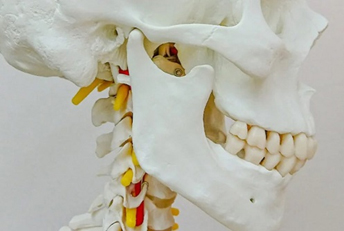

インプラントの構造

一般的に、インプラントは3つのパーツから成っています。

(1) インプラント本体(人工歯根)

顎骨に埋め込まれる部分です。ネジ状の形態をしており、骨としっかりと結合して一体化します。

(2) アバットメント(土台)

フィクスチャーと上部構造をつなぐ、接合部分です。

アバットメントとフィクスチャーは専用のネジで締結します。

(3) 上部構造(被せ物)

被せ物の部分です。

アバットメントと専用のネジで締結する場合と、アバットメントに歯科用セメントで合着する場合があります。

主にジルコニアという強度の高いセラミックで作製することが多いです。